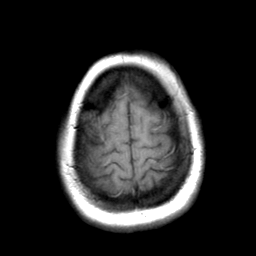

Cerebral hemorrhage, MR Study mr-t1 -- Slice #21

[Home][Help][Clinical] Slice 21